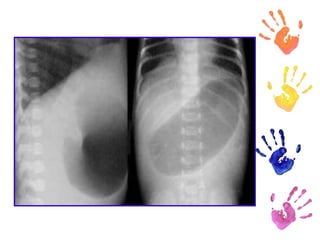

Diagnóstico Radiografías simples de abdomen Signo de doble burbuja El diagnóstico prenatal de atresia duodenal se puede realizar con facilidad mediante ecografía fetal.

Diagnóstico